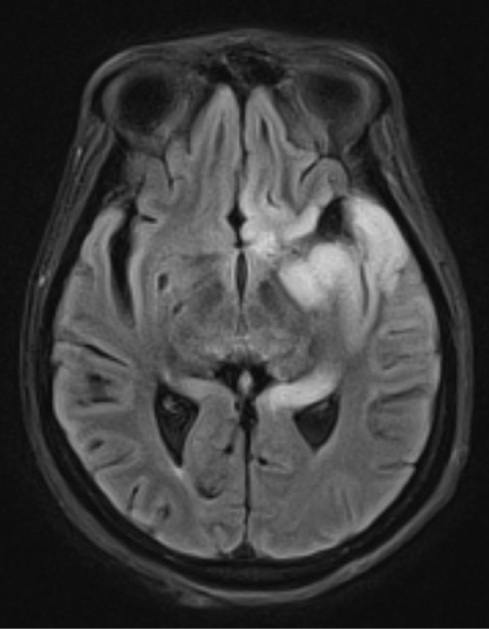

An 18-year-old man is evaluated due to worsening headaches. For the last several months, the patient has had intermittent, dull, occipital headaches, which are often brought on by physical activity, cough, or straining. The pain is usually accompanied by nausea and dizziness, and the symptoms spontaneously resolve after several minutes. There is no history of fever, chills, photophobia, vision disturbances, or focal weakness or numbness. He has no prior medical conditions and takes no medications. Vital signs are normal. Physical examination, including neurologic examination, shows no abnormalities. MRI of the head is shown in the image below:

This patient is at greatest risk for which of the following in association with his current condition?

A)Cardiac rhabdomyoma

B)Optic neuritis

C)Parathyroid adenoma

D)Syringomyelia

E)Vestibular schwannoma

This patient is at greatest risk for which of the following in association with his current condition?A)Cardiac rhabdomyoma